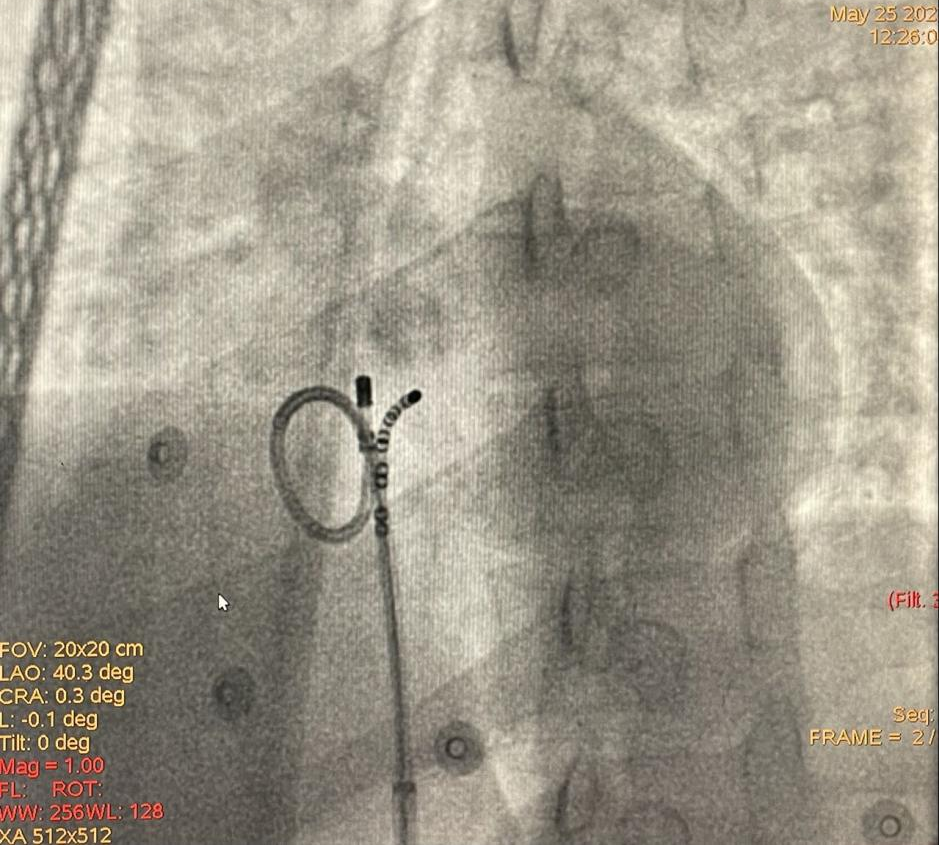

31岁男性患者,因心悸半年、胸闷痛3天于2022年5月22日入院,曾在山东某院就诊行动态心电图检查提示频发室早、室速,于是来我院寻求治疗。动态心电图提示有两种主要形态的室早,一种位于右室流出道,该形态有室速发作,另一种位于三尖瓣希氏束旁。患者上台后室早数量较少,行常规的激动标测作用有限,根据术前对室早的精准定位,结合起搏标测把第一种形态室早消融成功。随后标测第二种形态室早,位于希氏束上方,常规贴靠非常困难,术者采用少用的“α”弯稳定贴靠希氏束上方,最终消融成功。

希氏束旁室早消融靶点

希氏束旁室早“α”弯消融